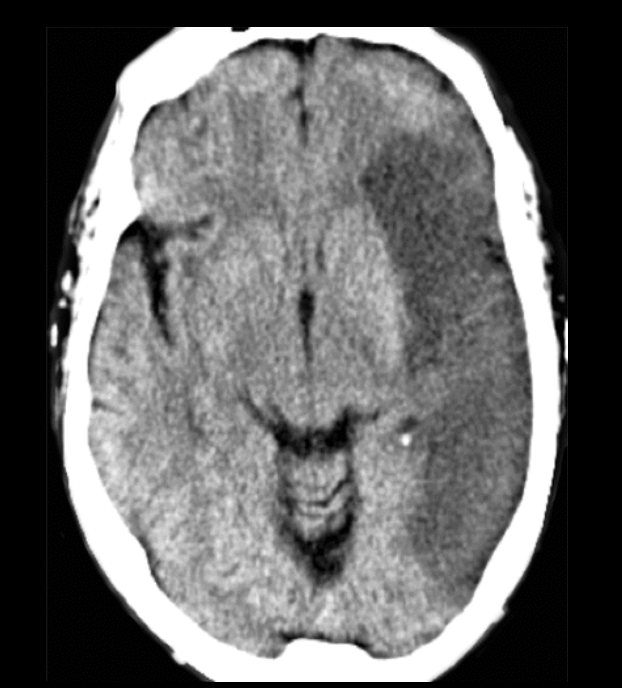

1

Q

A

EVC isquémico

Fase hiperaguda